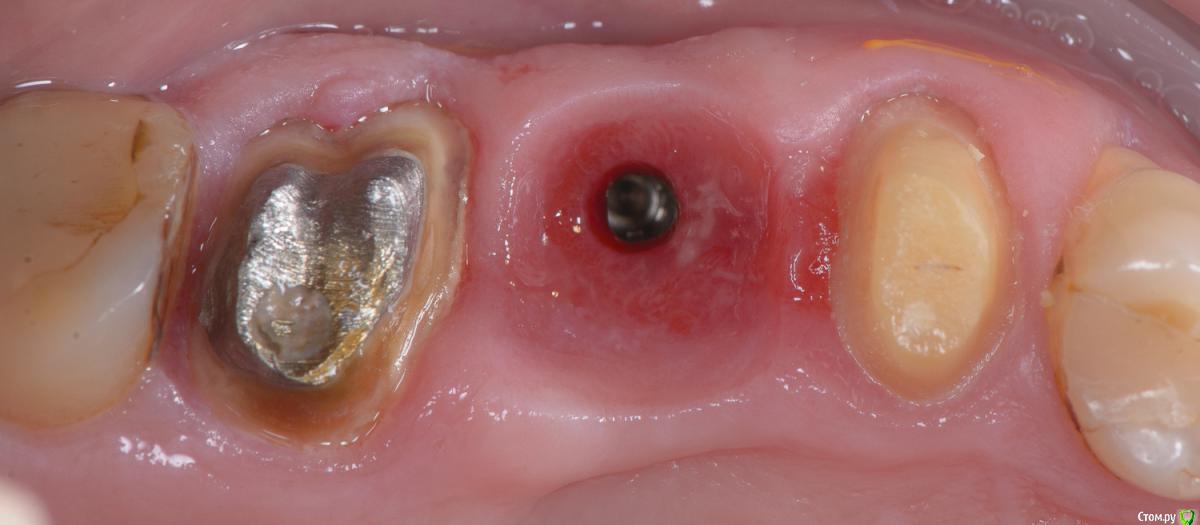

Популярный пост Mane Опубликовано 8 февраля, 2015 Популярный пост Поделиться Опубликовано 8 февраля, 2015 Зафиксировал в субботу. Собственно удалось размоделировать десну просто временной коронкой с заданным профилем прорезывания. Но для этого необходимо было выполнить ряд условий. Каких, доктора? http://i1218.photobucket.com/albums/dd412/Edikn73/emergence%20profile/Emergenceprofile001_zps040f2603.jpg http://i1218.photobucket.com/albums/dd412/Edikn73/emergence%20profile/Emergenceprofile002_zpsaa7acb0b.jpg http://i1218.photobucket.com/albums/dd412/Edikn73/emergence%20profile/Emergenceprofile003_zps259f0885.jpg http://i1218.photobucket.com/albums/dd412/Edikn73/emergence%20profile/Emergenceprofile004_zps6a15b901.jpg http://i1218.photobucket.com/albums/dd412/Edikn73/emergence%20profile/Emergenceprofile005_zps51a41bc2.jpg http://i1218.photobucket.com/albums/dd412/Edikn73/emergence%20profile/Emergenceprofile006_zps3c83a34d.jpg http://i1218.photobucket.com/albums/dd412/Edikn73/emergence%20profile/Emergenceprofile007_zpsba4d3d78.jpg 26 Ссылка на комментарий

Mane Опубликовано 10 февраля, 2015 Автор Поделиться Опубликовано 10 февраля, 2015 По поводу профиля прорезывание интересен Ваш протокол. Менялся ли ФДМ на более широкий, делались ли насечки на десне во время фиксации времяхи? Во первых - это заглубление платформы импланта - от будущего зенита до платформы - 3,5 мм . если этого не сделать - ничего не полуитсяпосле тонкого фдм зафиксировал временную коронку с небольшим надрезом по контактам. отдыхала с времянкой 1,5 мес.далее вы видели 1 Ссылка на комментарий

Евгений Ходыкин Опубликовано 20 февраля, 2015 Поделиться Опубликовано 20 февраля, 2015 Врачи, ответьте, плиз, на вопоосы выше. Какие д.б.исходники, кроме 3.5 мм?3.5 мм, как уже было сказано, это идеальное расстояние от зенита будущей реставрации до платформы имплантата. Но, как показывает практика, это, к сожалению, не всегда достижимо. Поэтому лучше всё-таки делать десневую аугментацию для максимального нивелирования возможных расхождений. имхо... 2 Ссылка на комментарий